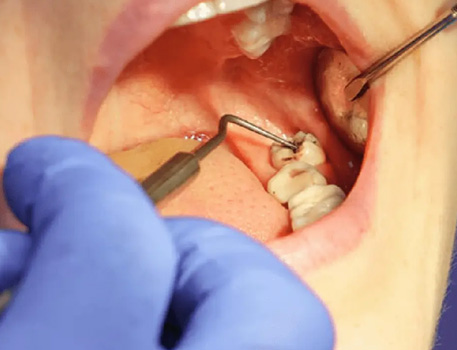

Gum Care: Professional cleaning to prevent infection.

Laser Therapy: Advanced laser treatment to reduce gum inflammation and promote faster healing.

Comprehensive oral examination with digital X-rays to assess the position and condition of your wisdom teeth.